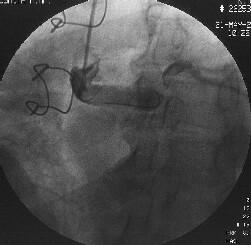

徢椺丗61嵨丄抝惈丅

婛墲楌丗58嵨帪偵DeBakey II宆偺媫惈戝摦柆夝棧偵偰Bentall弍(Piehler朄)傪巤

峴丅59嵨帪偵偼暊晹偵媫惈戝摦柆夝棧傪敪徢偟丄堦帪峈嬅屌椕朄傪拞抐偟偨偑偦

偺屻嵞奐丅

尰昦楌丗暯惉14擭5寧屵慜0帪傛傝摢栩晹捝偑弌尰偟丄嫻晹傊捝傒偑曻嶶偡傞傛偆

偵側傝7帪偵摉堾傪媬媫庴恌偝傟傑偟偨丅

棃堾帪尰徢丗寣埑86/66mmHg丆柆攺106/min丒惍丅岥怬偵僠傾僲乕僛傪擣傔偨丅怱

揹恾偱QRS暆偺奼戝偲I, aVL, V4-6偵ST忋徃傪擣傔丄媫惈怱嬝峓嵡偵傛傞怱尨惈

僔儑僢僋偲恌抐偟丄嬞媫僇僥乕僥儖専嵏傪巤峴偟傑偟偨丅

怱憻僇僥乕僥儖専嵏丗RCA偵嫹嶓昦曄傪擣傔傑偣傫偱偟偨偑丄LCx傊collateral傪

擣傔傑偟偨乮Figure1乯丅堷偒懕偄偰LCA偺憿塭傪帋傒傑偟偨偑丄JL僇僥乕僥儖偑

偳偆偟偰傕engage偱偒傑偣傫偱偟偨丅戝摦柆憿塭傪巤峴偟丄塃姤愲偺塃懁忋曽偵

憿塭嵻偺pooling傪擣傔傑偟偨乮Figure2乯丅擖岥晹偱姰慡暵嵡偟偰偄傞偲峫偊摨

晹埵偵懳偡傞僀儞僞乕儀儞僔儑儞傪巤峴偡傞偙偲偲偟傑偟偨丅擖岥晹偑塃懁忋曽

偵懚嵼偡傞偨傔丄僈僀僨傿儞僌僇僥乕僥儖偼丄JR僇僥乕僥儖傪巊梡偟傑偟偨

乮Figure3乯丅

側偍丄恖岺寣娗偺擖岥晹偺摨掕偵旕忢偵擄廰偟丄専嵏奐巒屻偡偱偵栺30暘偑宱夁

偟偰偄傑偟偨丅屇媧忬懺偑偝傜偵埆壔偟偮偯偗偨偨傔丄恖岺屇媧娗棟偲偟傑偟

偨丅寣埑傕掅壓偟偰偄傑偟偨偑丄DOA5兞掱搙偱80-90戜傪堐帩偟偰偄傞忬嫷偱偟

偨丅IABP偺憰拝傕峫偊傑偟偨偑丄戝摦柆夝棧偑懚嵼偟偰偄傞偨傔巊梡偟傑偣傫偱

偟偨丅

姤摦柆僀儞僞乕儀儞僔儑儞丗僈僀僨傿儞僌僇僥乕僥儖偺engage偑埆偄偨傔丄儔僕

僆僼僅乕僇僗丒儚僀儎乕偱僇僥乕僥儖傪屌掕偝偣側偑傜彊乆偵儚僀儎乕傪恑傔偰

偄偔偲丄彮偟偯偮寣娗偑憿塭偝傟傞傛偆偵側傝丄恖岺寣娗偲LMT偺暙崌晹偵崅搙

嫹嶓傪擣傔傑偟偨乮Figure4乯丅傑偨丄嵍姤摦柆撪偵嫄戝側寣愷傪擣傔傑偟偨丅

摉帪寣愷媧堷偺僨僶僀僗偑側偔丄媧堷偼偱偒傑偣傫偱偟偨丅暙崌晹偵懳偟偰丄

MAVERICK4.0mm偱POBA傪峴偄丄偦偺屻LAD偵嫄戝側寣愷偑棳傟偰偄偔偺偑妋擣偝傟

傑偟偨乮Figure5乯丅NIR4mm僗僥儞僩傪棷抲偟暙崌晹嫹嶓偼夵慞偟傑偟偨偑丄LAD

偺no flow傪擣傔傑偟偨丅nicorandil偍傛傃UK傪姤拲偟偨偲偙傠丄flow偑夵慞偟

偨偨傔庤媄傪廔椆偟傑偟偨乮Figure6乯丅